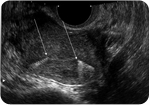

Three months after the Essure® procedure, the gynecologist performs an Essure Confirmation Test to confirm the correct position of the implants and that the tubes are completely blocked thus indicating permanent contraception. The Confirmation Test is carried out via an x-ray of the abdomen or an ultrasound scan of the uterus. The implants can be viewed and assessed as to their position and whether or not the tubes are completely blocked. When the test confirms that the implants are well positioned and the tubes are blocked then test results show that the woman has zero chance of falling pregnant.

- One month after the procedure, the gynecologist schedules a check-up and will usually perform an ultrasound scan of the pelvic area to verify that the implants are in the correct position.